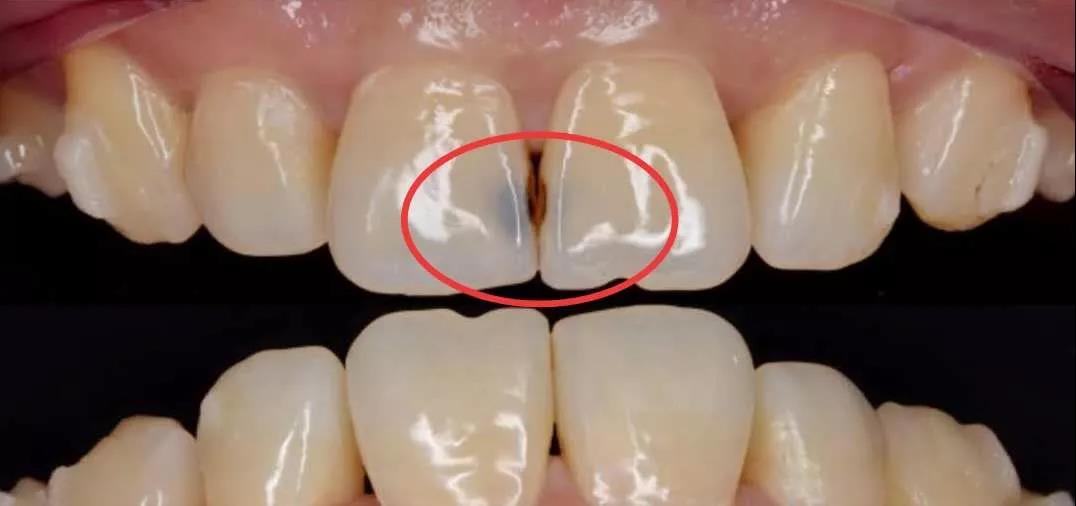

红圈内就是邻面龋

就比如邻面龋,它是发生在两颗牙齿相邻的区域的一种被蛀情况,因为牙刷清洁不到一部分牙缝,久之细菌在其间繁殖就致龋了。

预防邻面龋,需要使用牙线清洁牙缝间的食物残渣和细菌。